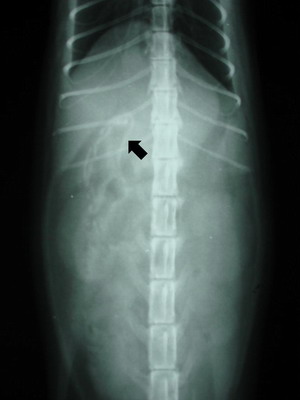

Na rentgenových snímcích bylo naštěstí lineární cizí těleso viditelné a nacházelo se na přechodu žaludku a dvanáctníku. Ve většině případů se umělá nebo gumová cizí tělesa na rentgenových snímcích rozeznat nedají.

RTG ukazující cizí těleso na přechodu žaludku a dvanáctníku RTG ukazující cizí těleso na přechodu žaludku a dvanáctníku